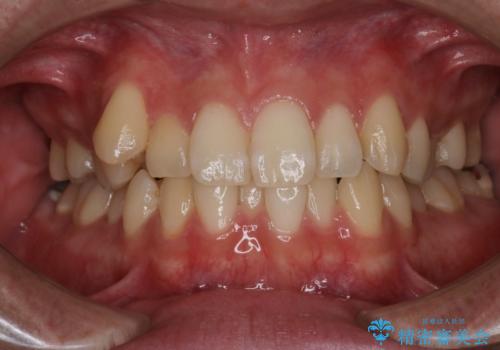

- 前歯の叢生を主訴に来院されました。非抜歯でインビザラインで治療をしました。

叢生はIPRをし、並べました。この患者様はオープンバイトだったため歯を並べる過程でかみ合わせも治しました。